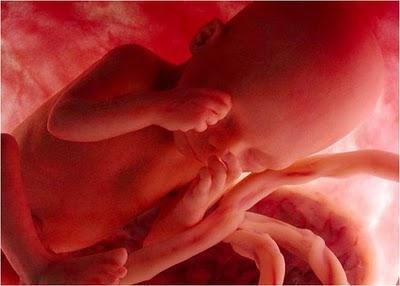

Las imágenes utilizadas en esta presentación son parte del documental "En el vientre materno" producido por National Geographic.

Son imágenes obtenidas a través de una micro-cámara introducida en el útero de una gestante. Gracias a las modernas técnicas fotográficas es posible acompañar el fascinante proceso de gestación de un bebé.

ÉL COMPLETA 24 SEMANAS.DE SUS ÓRGANOS, SOLAMENTE LOS PULMONESNO ESTÁN COMPLETAMENTE FORMADOS.

EN ESTA ETAPA YA MUEVE SUS BRAZOS Y SUS PIERNAS, GUIÑA LOS OJOS, CHUPA SUS DEDOS E, INCLUSIVE,TIENE SUS PRIMEROS ACCESOS DE HIPO.

ESTÁ CADA VEZ MÁS CONSCIENTEDE EL ESPACIO QUE LO RODEA.

COMO TODOS LOS FETOS, PASA LA MAYOR PARTE DEL TIEMPODORMIDO Y, CUANDO DUERME, NADA CONSIGUE DESPERTARLO.LLEGA INCLUSO A SOÑAR.